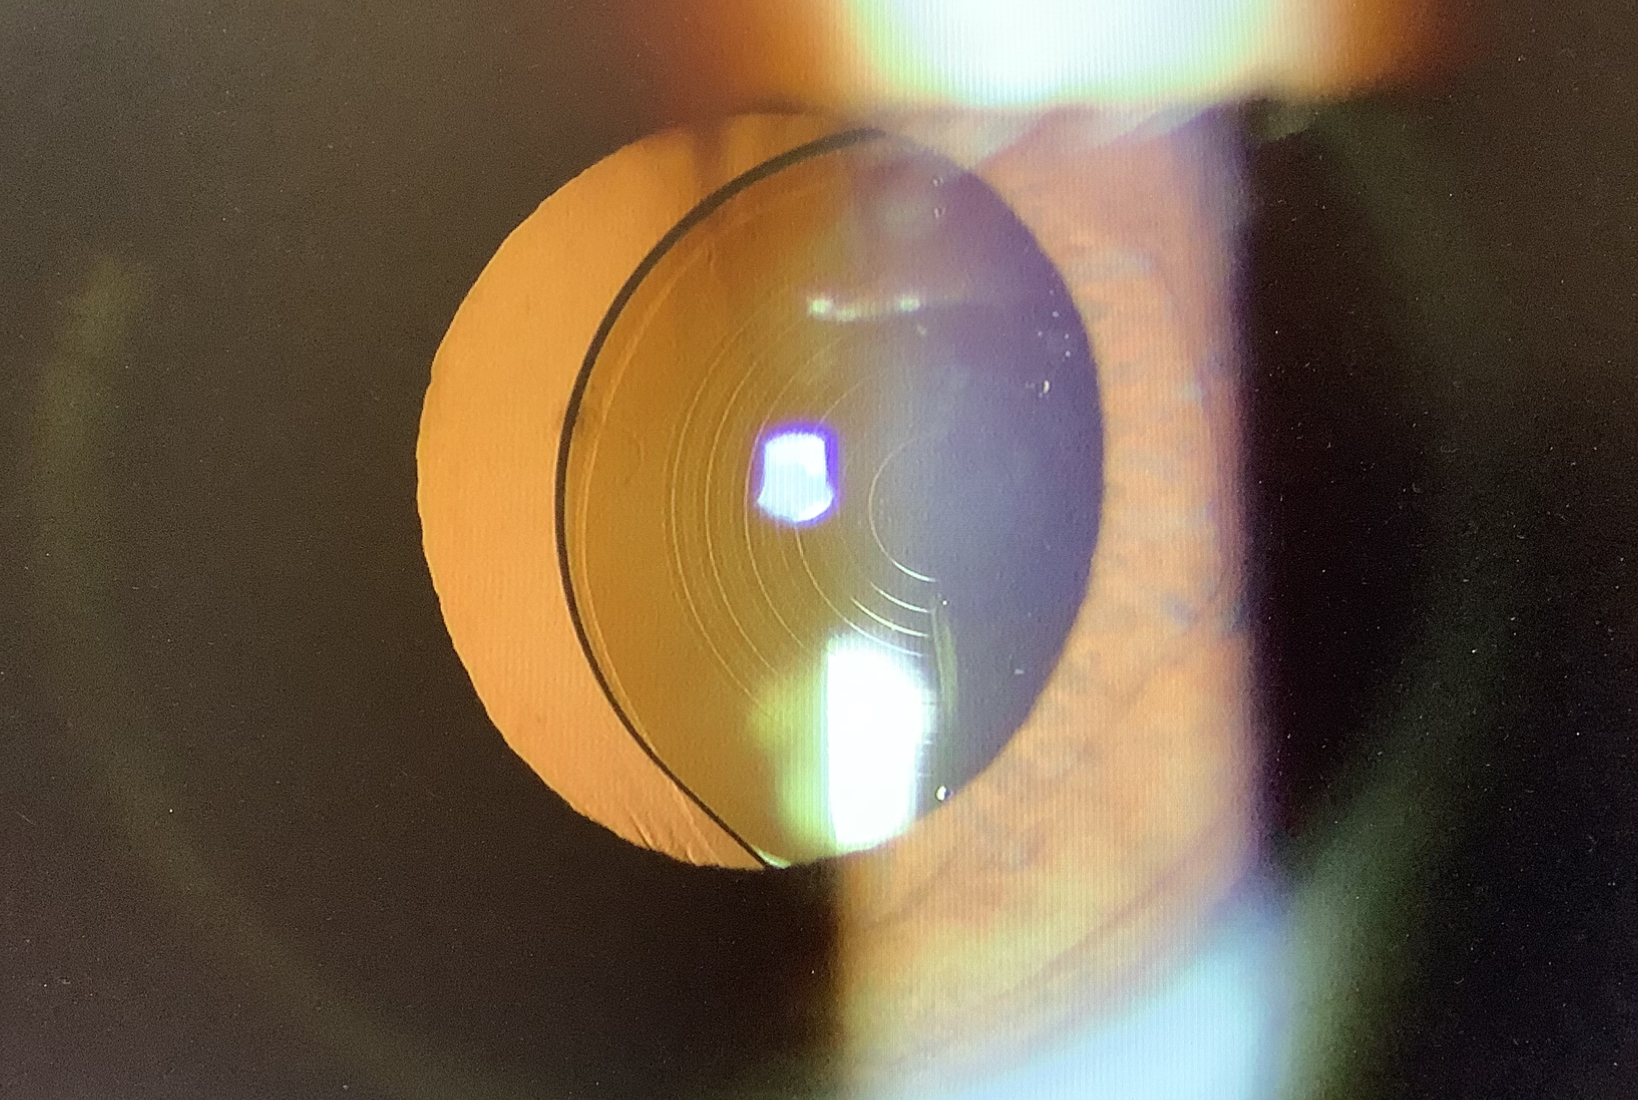

今日の外来では、昨年の春に当院で多焦点レンズ(パンオプティクス)を使った白内障の手術を受けていただいた60代前半の男性の方が『1か月くらい前からレンズが動いているような感じ。上を向いた時にレンズの影が見える気がする。』ということでいらっしゃいました。白内障の手術の後に“レンズが動いている”と心配されていらっしゃる方もいますが、実際にレンズがズレてしまっている人はそうはいません。でも、今日の患者さんは実際にレンズの偏位が起こっていました。こうなると、今入っているレンズを取り出し、新たなレンズを眼の壁に固定する“強膜内固定”という手術を予定させていただきました。

普通の白内障の手術であれば、患者さんの希望や眼の状態に応じて、眼内レンズの選択の余地が色々ありますが、強膜内固定では3ピースタイプのレンズを使わないとならず、3ピースタイプのレンズは単焦点しかなく、乱視矯正のトーリックタイプもなく、レンズ選択の制限が出てしまいます。強膜内固定で使えるレンズでも多焦点やトーリックが使えればいいなとは思いますが、強膜内固定では、レンズを2点で固定するため、どうしてもレンズの傾きや中心からのズレが多少出てしまい、傾斜や偏心が出やすく、多焦点レンズの効果が十分に発揮できないどころか、見え方がブレてしまったり、夜の光が余計におかしく見えてしまう恐れがあるため、強膜内固定での多焦点レンズの使用は現実的には難しいかと思います。乱視用のトーリックレンズも角膜の乱視の方向に合わせてレンズを入れる必要があるのですが、強膜内固定では、レンズを固定しやすい位置がある程度決まっていますし、仮に自由な位置に固定できたとしても、乱視の軸とトーリックの軸をぴったり合わせることは簡単ではありません。単純に強膜内固定用の多焦点やトーリックの眼内レンズ自体は作ることができても、実際に眼に入れた時に、それで十分な効果を得ることが難しいため、そのようなレンズがないのがないのが現状かと思います。遠方も近方も見えるようにすることや、角膜乱視の影響は残ってしまうという制限はありますが、眼内レンズがズレてしまった場合は、手術をせざるを得ませんから、使える単焦点レンズでなるべく不便の出にくいピント設定で手術をするしかないかと思います。今日の患者さんも片眼は多焦点レンズが入っていますので、強膜内固定する方の眼は遠方にピントを合わせるレンズ選択をしました。角膜乱視があるので本当はトーリックレンズが使いたいところですが、なるべく乱視が増えないような手術したいと思います。